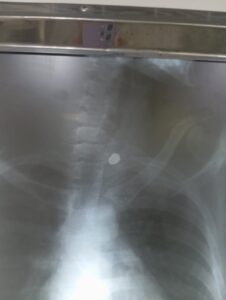

O Portal Raízes teve acesso, com exclusividade, ao exame de raio-X que mostra o projétil alojado no corpo da vítima. De acordo com Milene, por poucos centímetros o disparo não causou uma lesão ainda mais grave ou até fatal.

Apesar do ocorrido, o estado de saúde de Moisés é considerado estável. Ele deverá passar por uma tomografia para avaliar a necessidade de retirada do projétil. Caso não haja comprometimento de órgãos vitais, existe a possibilidade de a bala permanecer alojada no corpo.